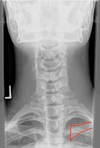

AP LOWER CERVICAL LANDMARKS

c3-t2 vertebral bodies

73

A-P lower cervical view

uncinate processes c3-c7

74

articular pillars

75

TVP's of cervical + thoracic spine

76

SP's of c2-t12

77

clavicles

78

angle of mandible

79

base of occiput

80

pedicles of c1-t12

81

ribs

82

tracheal air shadow